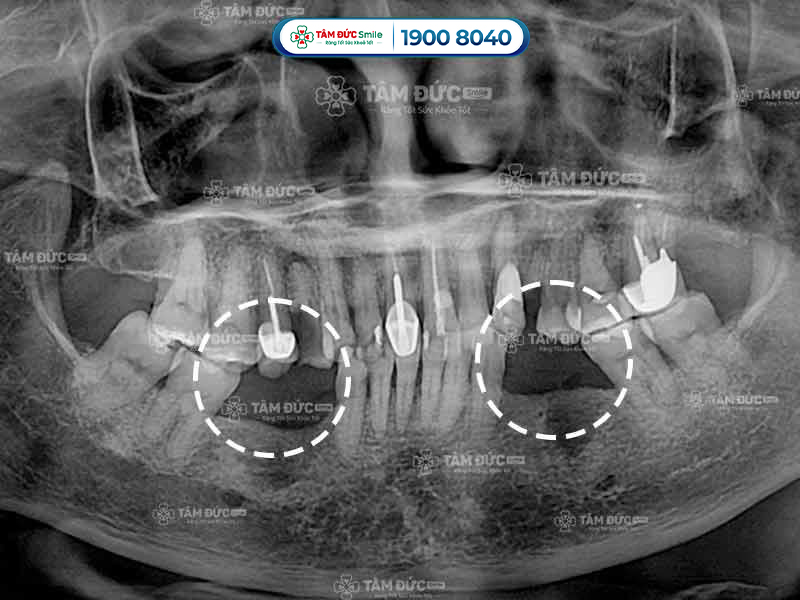

Trụ Implant kém chất lượng sẽ nhanh chóng bị cơ thể đào thải ra ngoài, làm Quý khách bị chảy máu chân răng hoặc viêm nướu. Kết quả chụp phim X-Quang cho thấy xương không bám vào trụ Implant, lúc này Quý khách cần phải trồng răng lại từ đầu.